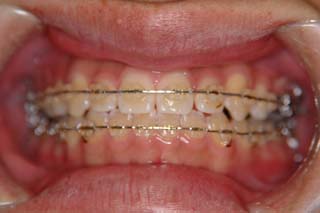

はならび自体は僅かな叢生が見られるだけなのですが、実はほとんどの歯が噛めていません。奥歯ばかりで強く噛んでいる状態です。また、顎関節症でよく見られる首、肩の具合が悪い という症状も見られました。かみ合わせとの関連性については不明ですが、適正な咬合構築に伴って、これらの症状が改善する事をよく経験します。

マルチブラケット装置でまっすぐに並べただけの状態です。なるほど、まるで噛めてない状態なのがよく分かります。ここでよく有りがちな矯正治療だと、上の前歯と下の前歯にゴムを1日中かけて噛ませていくのですが、それでは以前と同じく、関節をずらして噛むだけの人になってしまうでしょう。特に垂直的なコントロールが必要と考えられた上顎左側に オーソアンカー SMAPシステム の植立を行いました。

次第にアゴのズレが取り除かれて、しっくり噛めるかみ合わせに変化していっています。長い年月をかけて修飾されてきた顎関節の環境はなかなか良い形に変わりませんので、時間をかけて改善を行います。